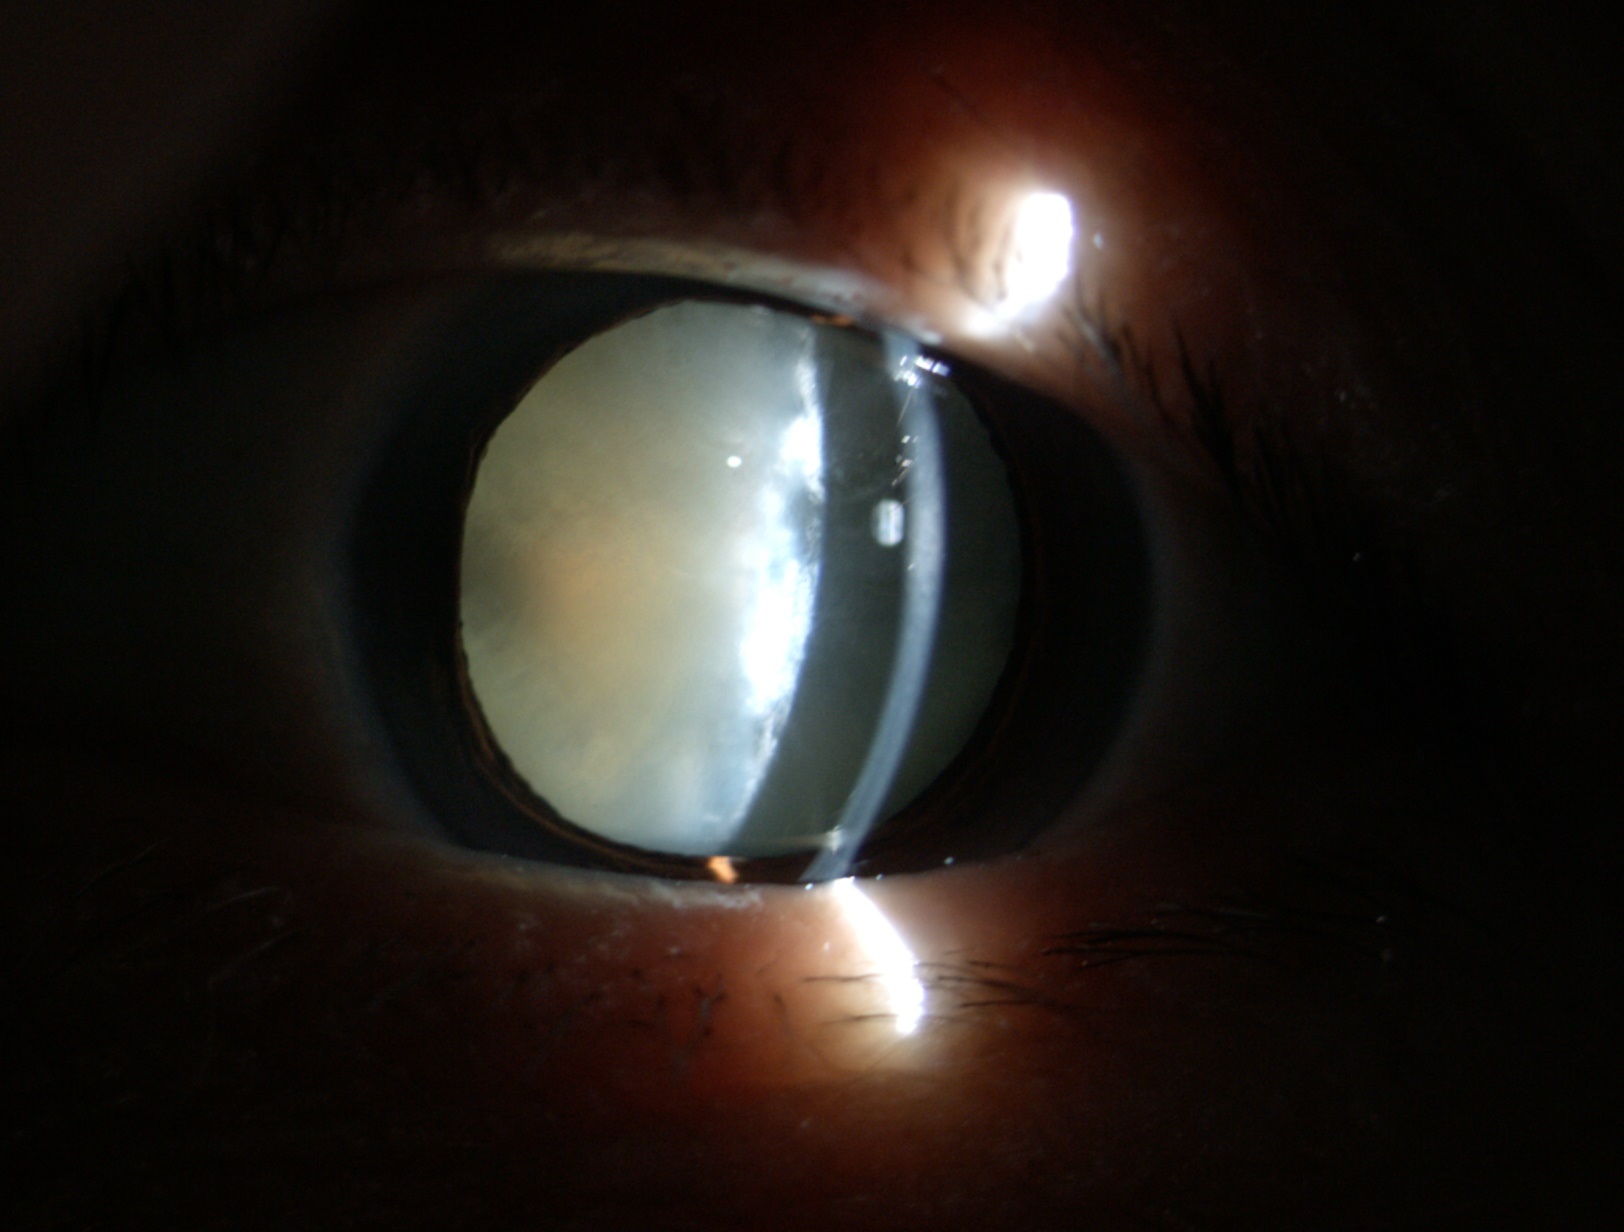

老年性白內障